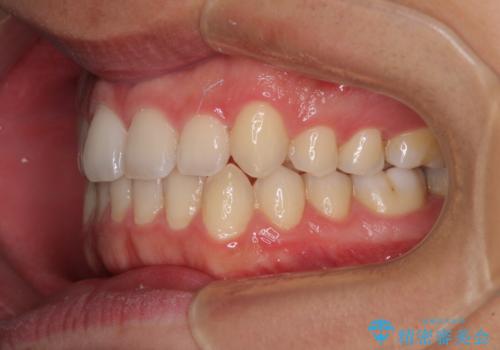

狭い歯列と前歯のデコボコ インビザラインによる矯正治療

- 上下前歯のデコボコを気にして来院された患者様です。

インビザラインによる上下歯列の拡大と、IPR(歯と歯の間を削る)にるスペースの獲得により、前歯のデコボコと狭い歯列を改善することとしました。

比較的軽度な歯列不正であったため、治療期間はそれほど長くはならないと予想されました。

しかしながら、あまりしっかりとマウスピースを装着していなかったため、思いの外期間が長引いてしまいました。

また、仕上がりの歯列にも若干の叢生が残ってしまいました。